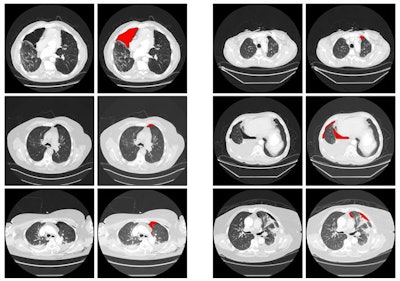

After classifying patches of the images based on their probability of pneumothorax, the seven-layer CNN generates "heat maps" on the images to display the size of the pneumothorax area, the relative location of the region to the lung boundary, and a shape descriptor. A support vector machine classifier was then trained to use this data to classify the chest CT scans as either positive or negative for pneumothorax.

In testing, the deep-learning algorithm detected all 122 cases of pneumothorax and had 16 false positives (88.5% specificity). The 16 false-positive results were related to either metal artifacts or bullae associated with chronic obstructive pulmonary disease. However, radiologists can easily recognize these false-positive findings, Thrall said.